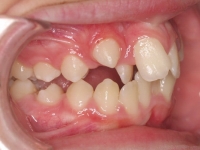

Paciente de 15 años “no le gusta su sonrisa”. La paciente presenta:

- Clase I esquelética con tendencia a Clase III

- Clase I molar

- Perfil con protusión mandibular

- Laterales enanos

- Apiñamiento

El tratamiento se hizo con brackets de autoligado y tuvo una duración de año y medio. Al finalizar, su dentista le hizo reconstrucción con carillas de los incisivos laterales 12.22.

Ahora la paciente está en contención con férulas superior e inferior más contención fija inferior.